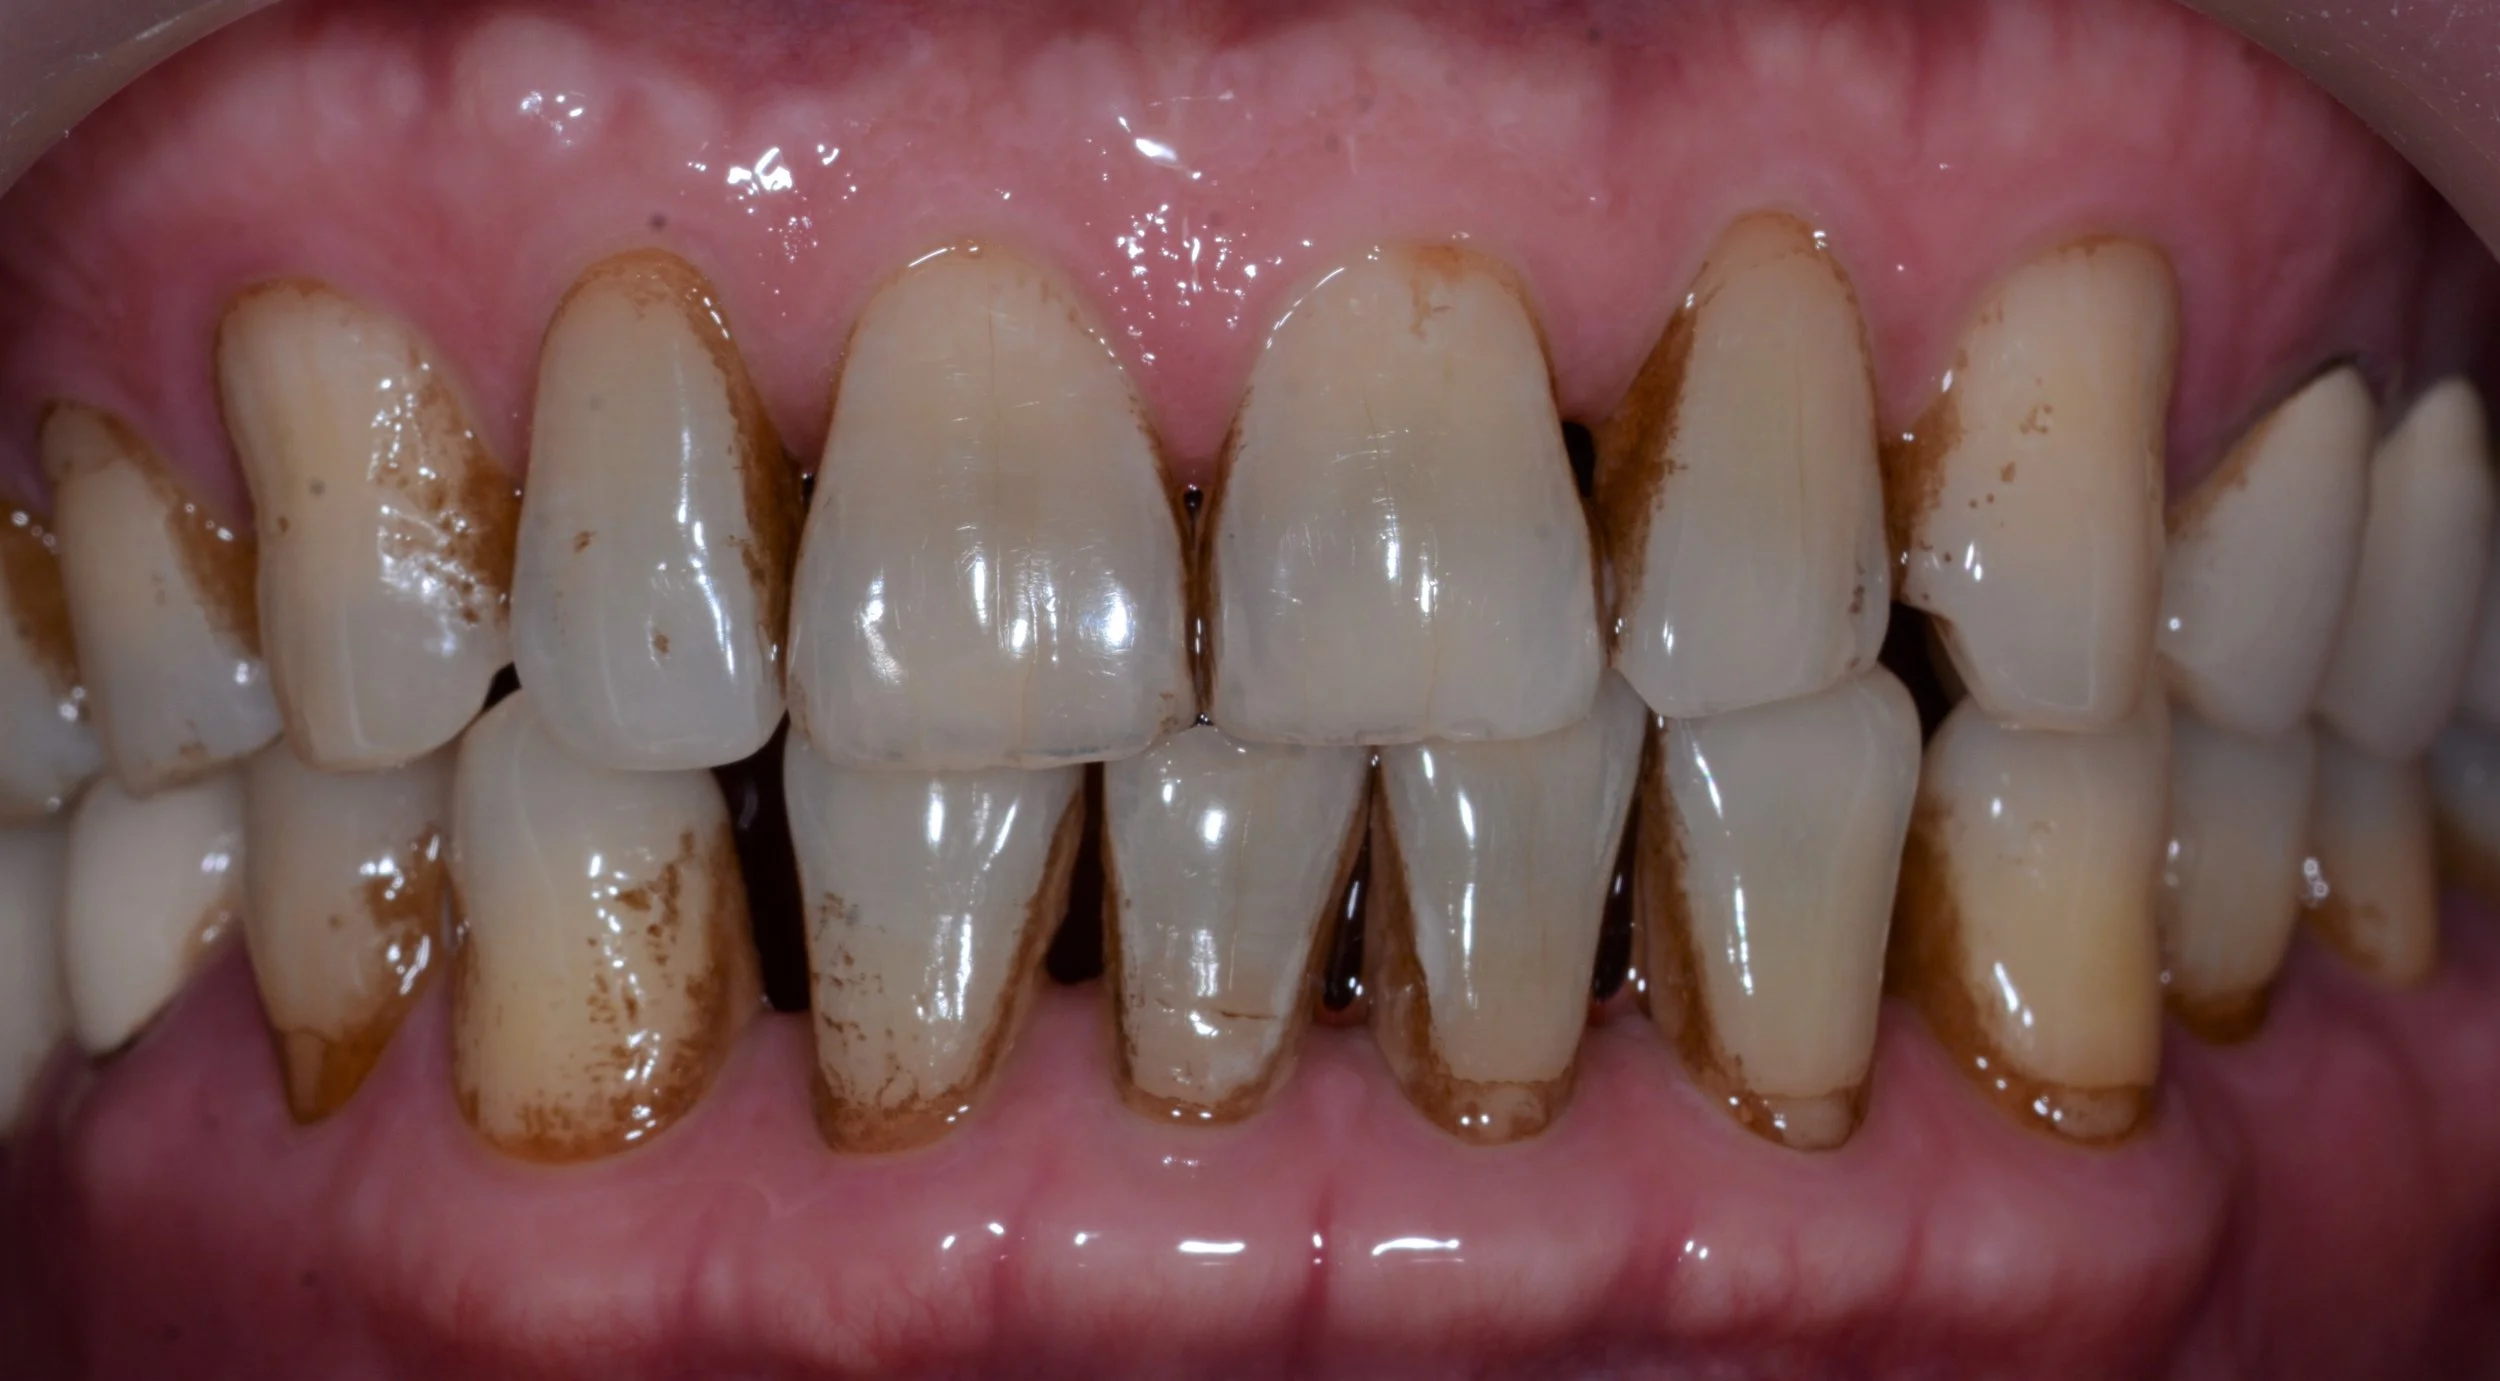

BEFORE

SINGLE FRONT TOOTH IMPLANT

Jason Hp PA Preop.jpg

Failing Natural Central Incisor

(Upper front tooth)